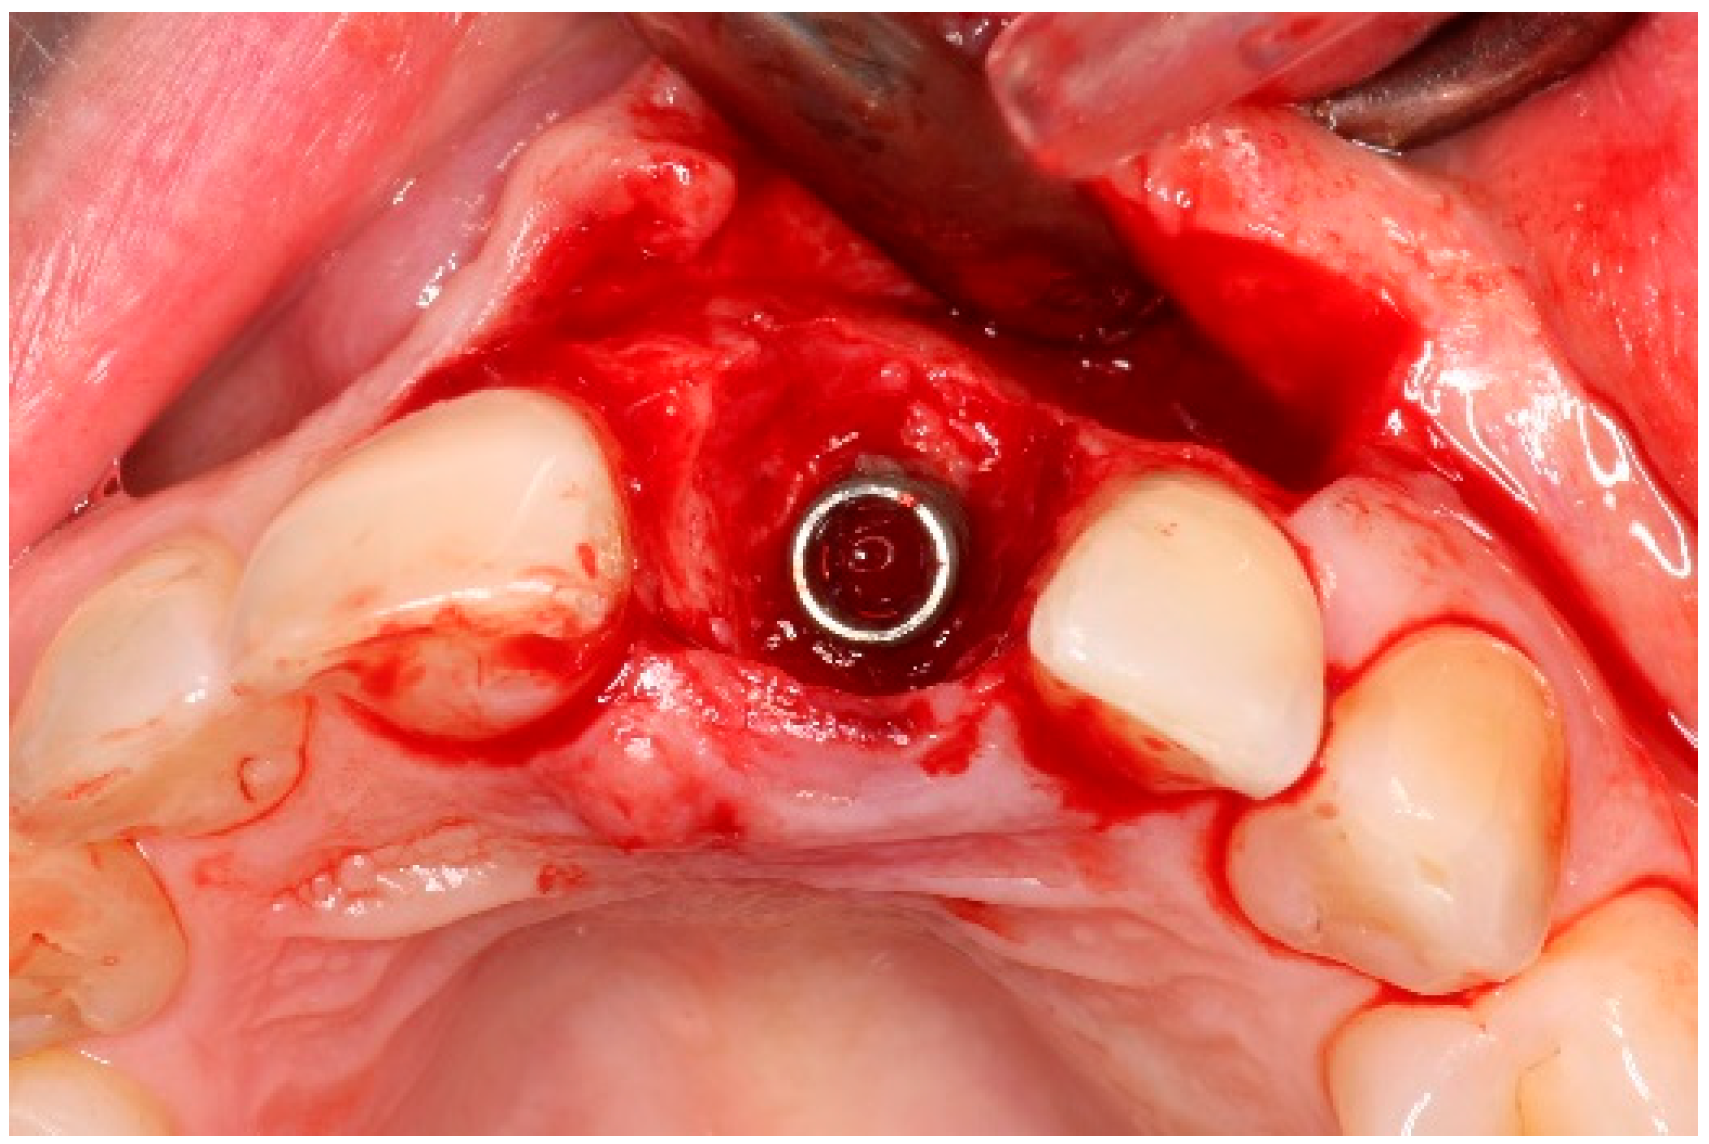

4. Timeline and Diagnostic Assessment

5. Therapeutic Intervention

5.3. Surgical Treatment